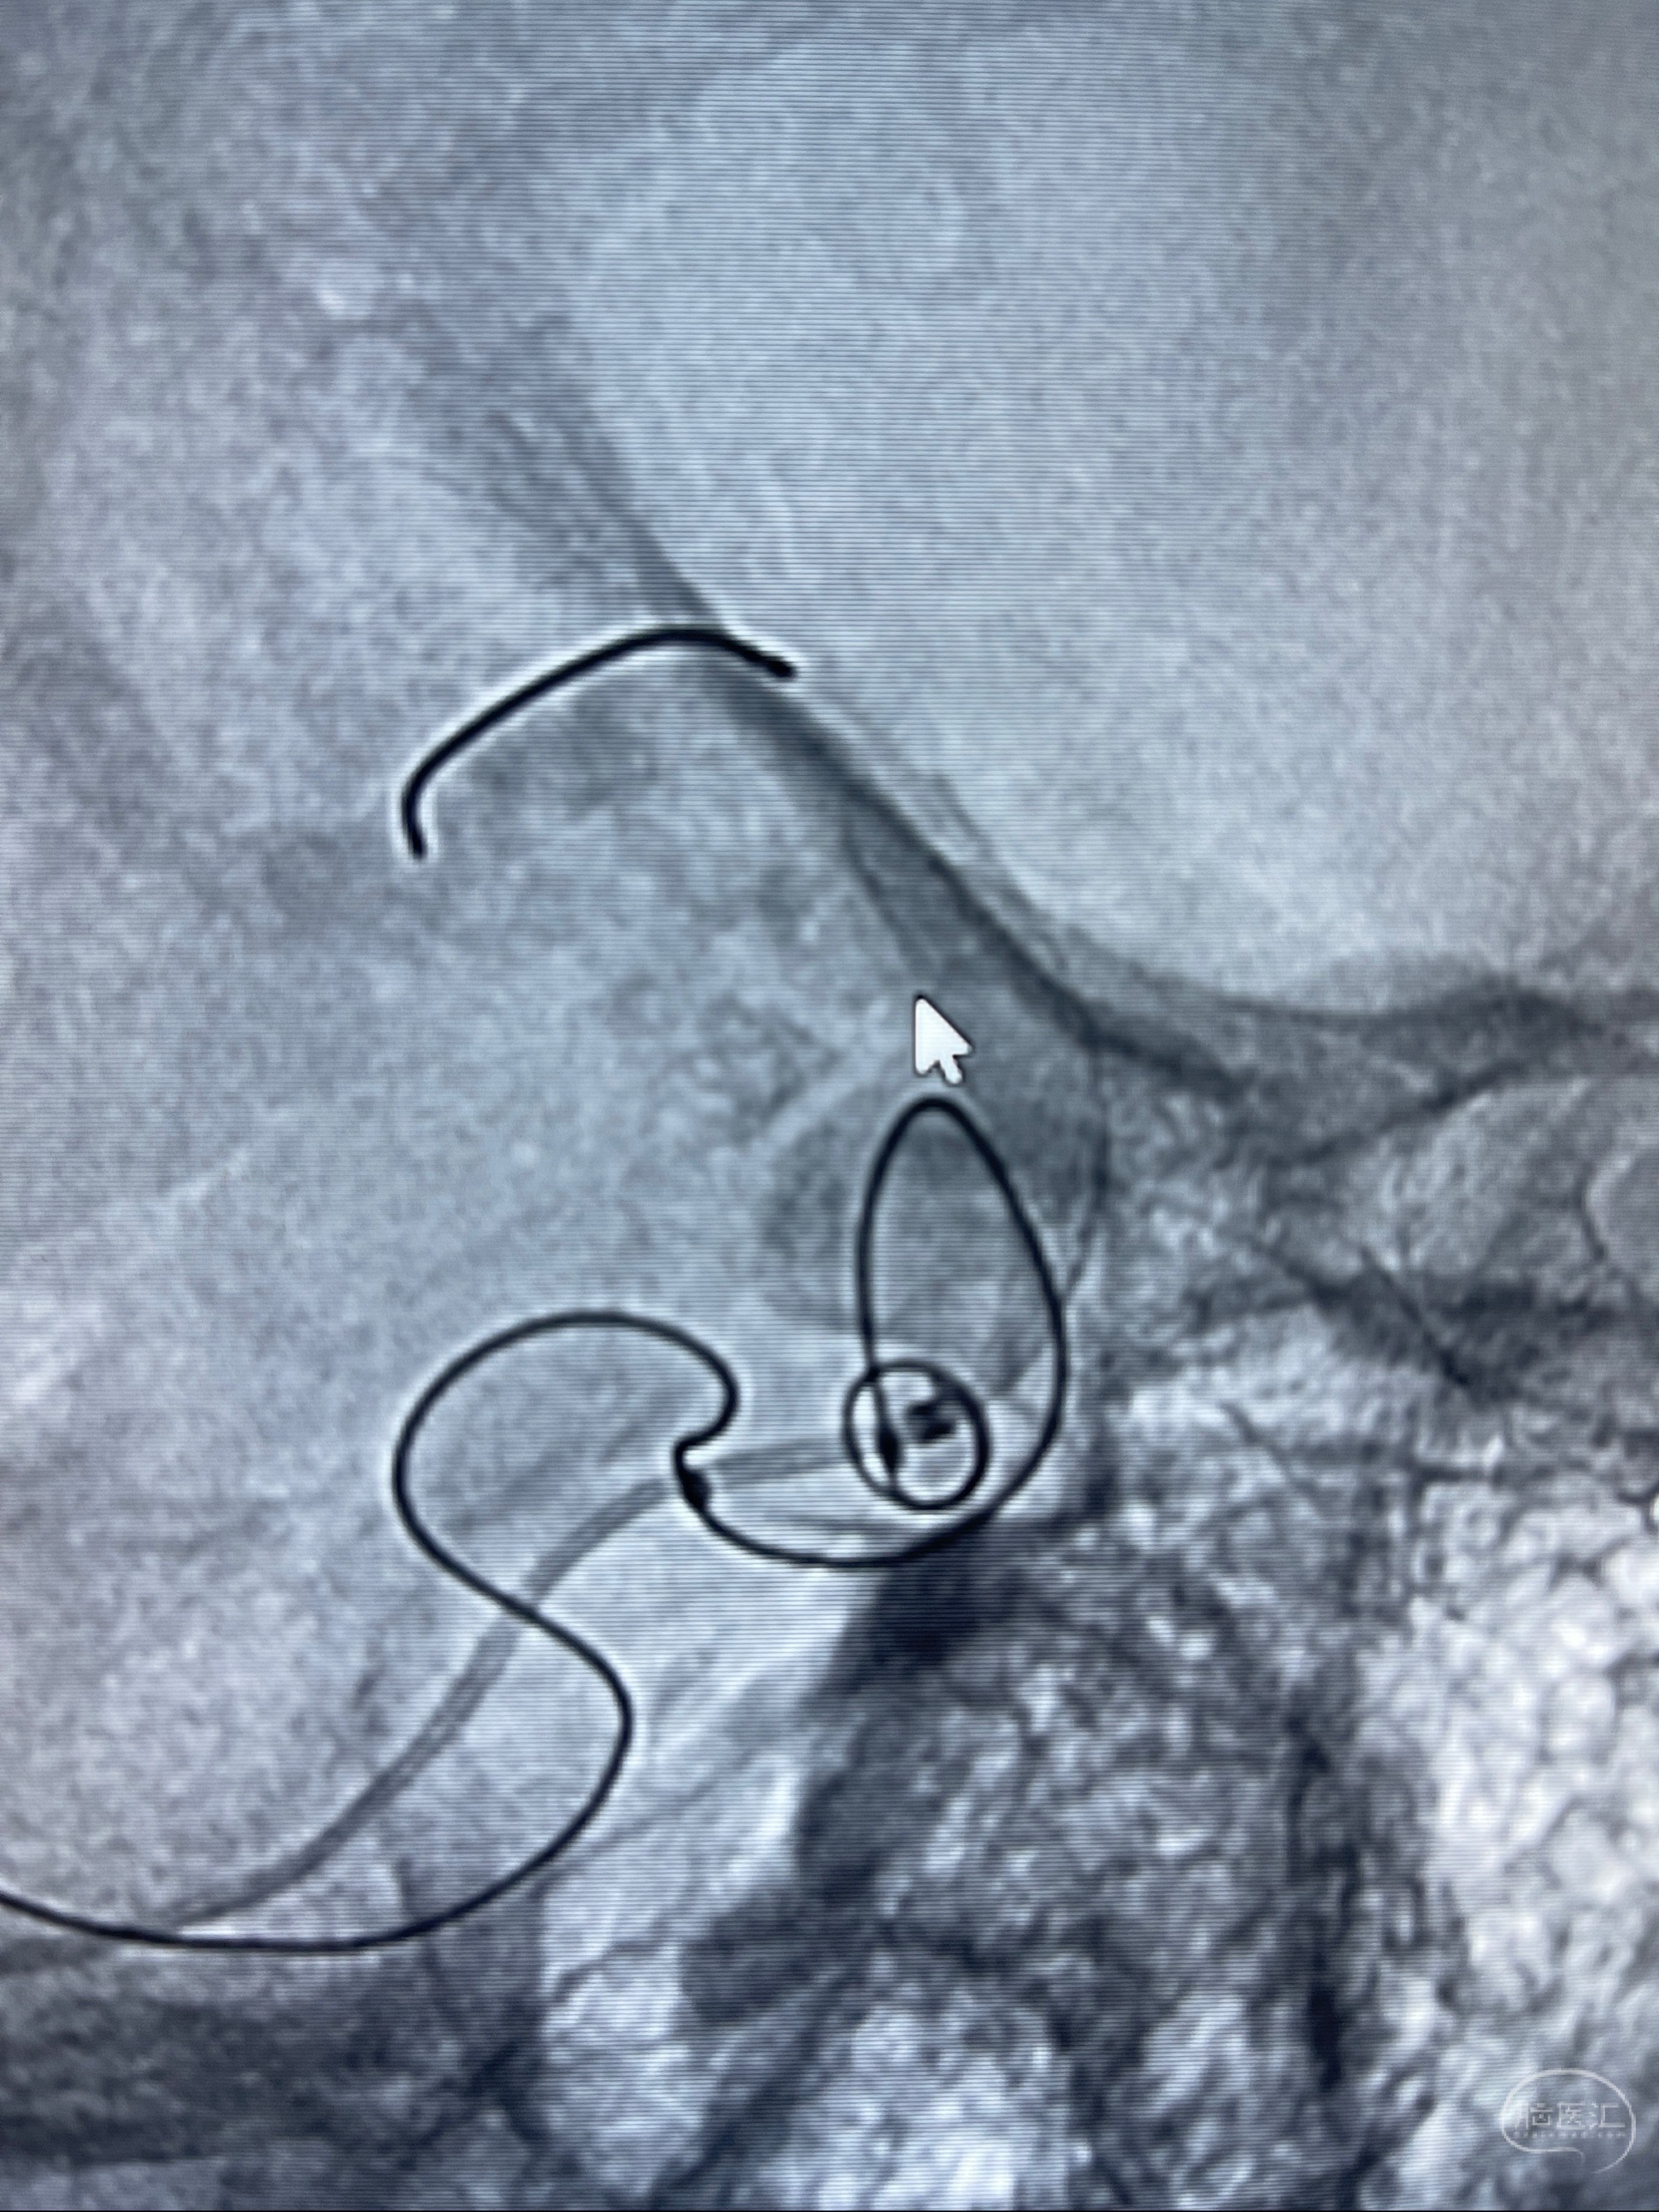

2023-07-27全脑血管造影:双侧颈内动脉眼动脉段动脉瘤,右侧较大

2023-08-01全麻下行双侧颈眼动脉瘤支架辅助栓塞

- pipeling4.5-20mm

- pipeline 4.0-20mm